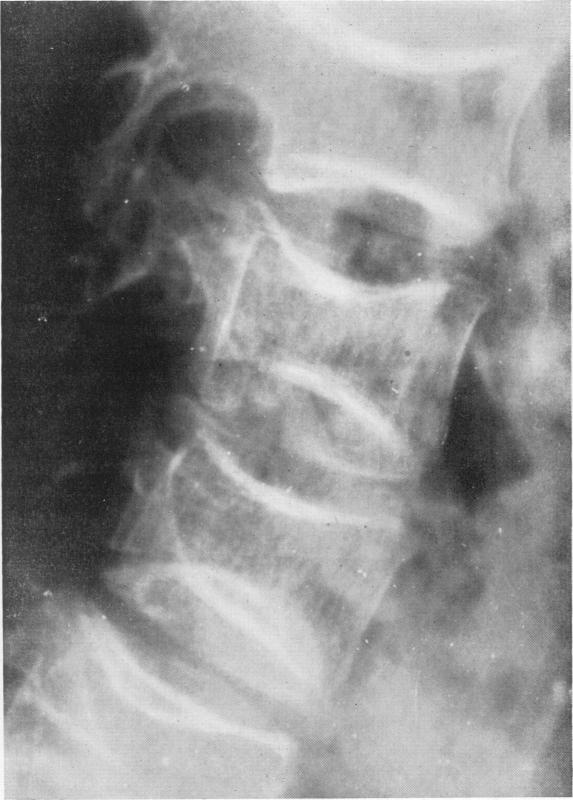

The bone changes in sickle cell anaemia.

Ann R Coll Surg Engl. 1956 Nov;19(5):296-315.